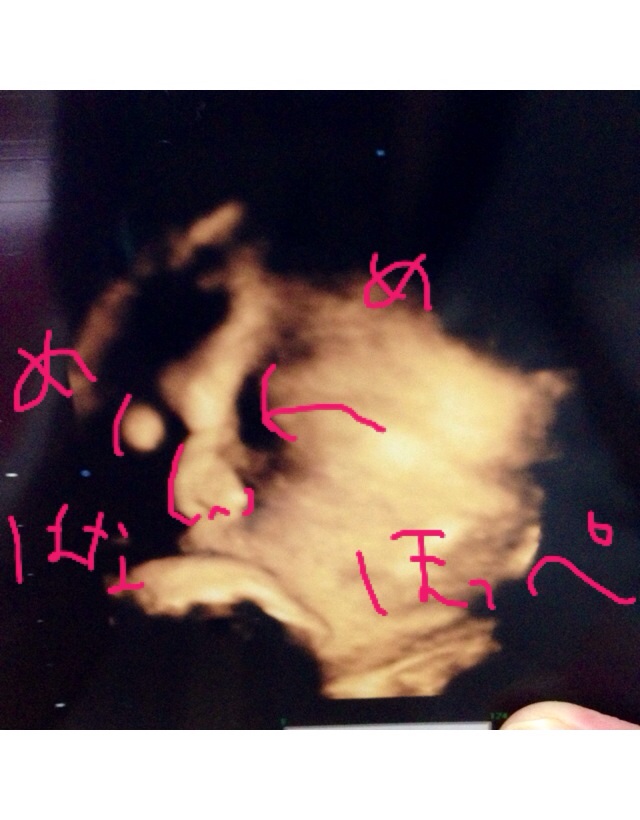

もう上手くエコーに映らなくなってきたよーーぶしゃいく。

推定3021g

あ、この産院には先生が3人いるのですが、前に聞いた先生じゃなかったから、また「うちの子、鼻 高いですよね!」って聞いちゃいました。←しつこい笑

だって嬉しいんだもん。